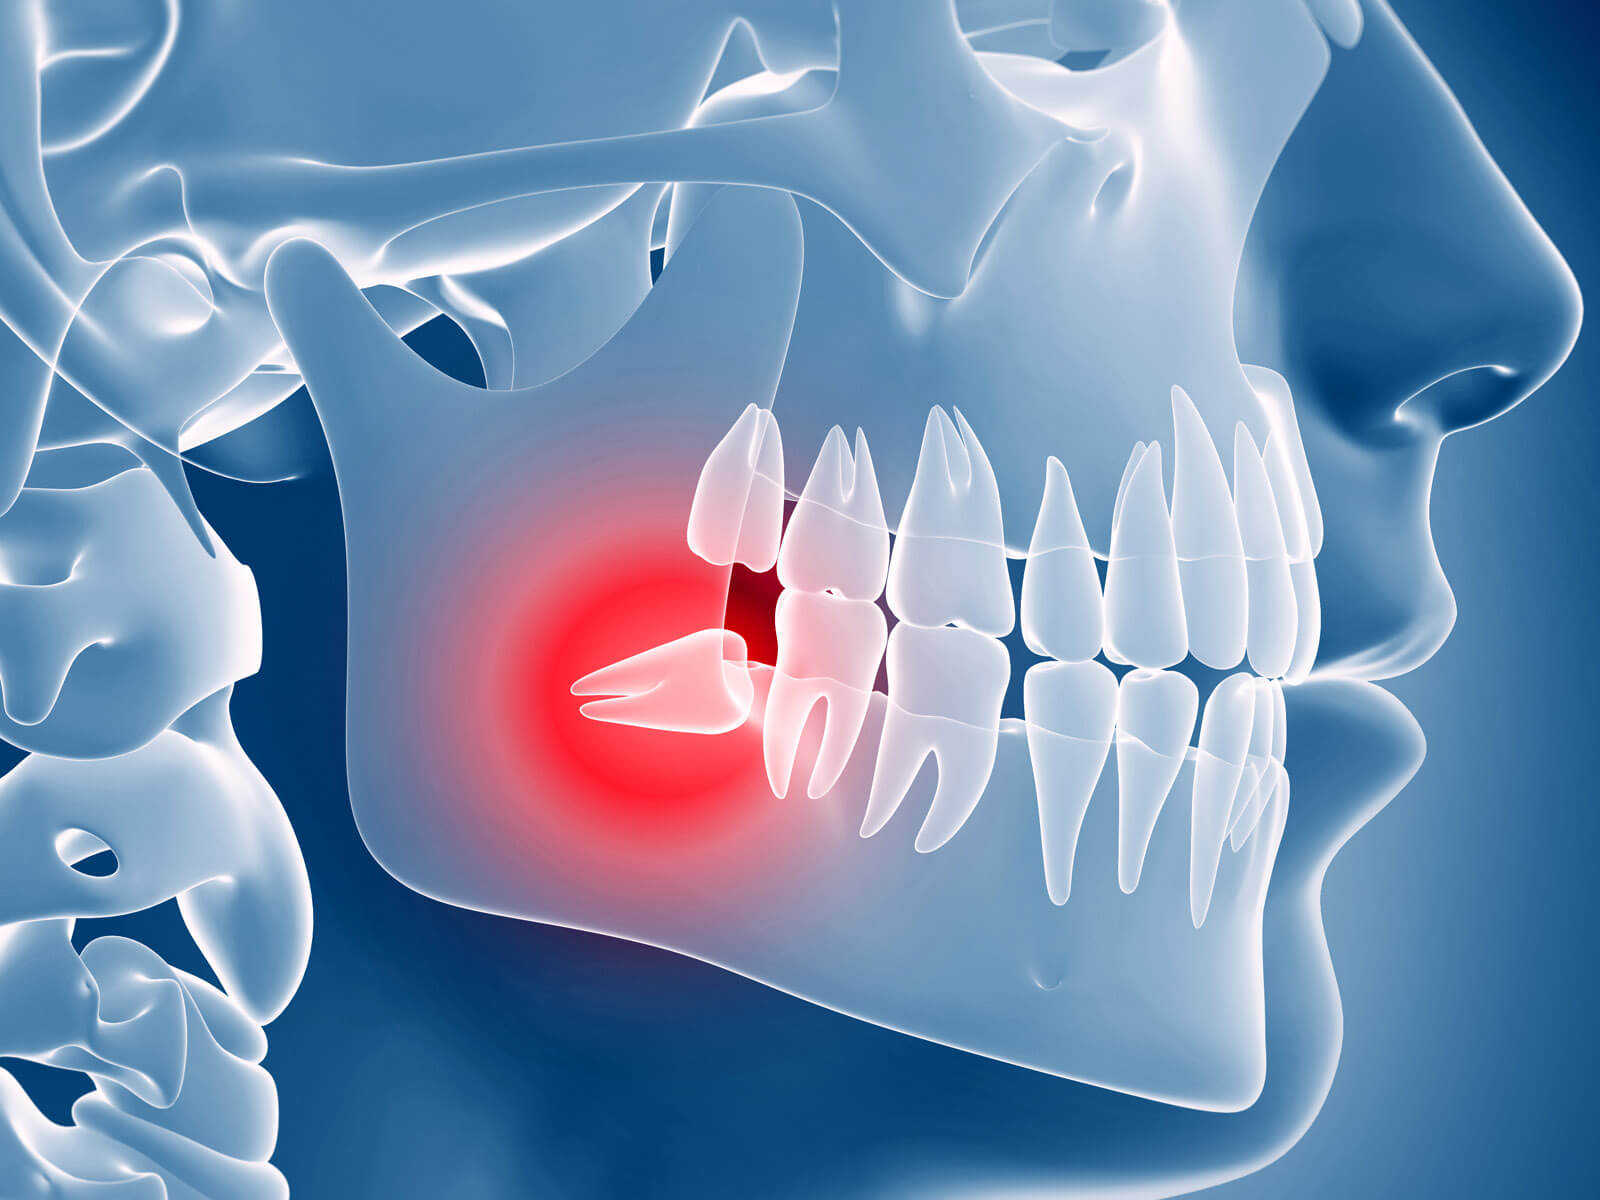

Diş ağrısına ne iyi gelir Diş ağrısına ne iyi gelir sorusunun en hızlı cevabı, ağrının şiddetini geçici olarak azaltmak için soğuk kompres uygulamak, ılık tuzlu su ile gargara yapmak ve gerekli durumlarda ağrı kesici kullanmaktır ancak bu yöntemler yalnızca kısa…

20’lik Diş Çekim Ücreti Antakya 20’lik diş çekim ücreti Antakya bölgesinde diş ağrısı, şişlik, baskı hissi veya gömülü diş problemleri yaşayan hastalar tarafından en çok araştırılan konular arasında yer almakta olup bu işlemin fiyatının sabit olmadığı ve her hastanın klinik…